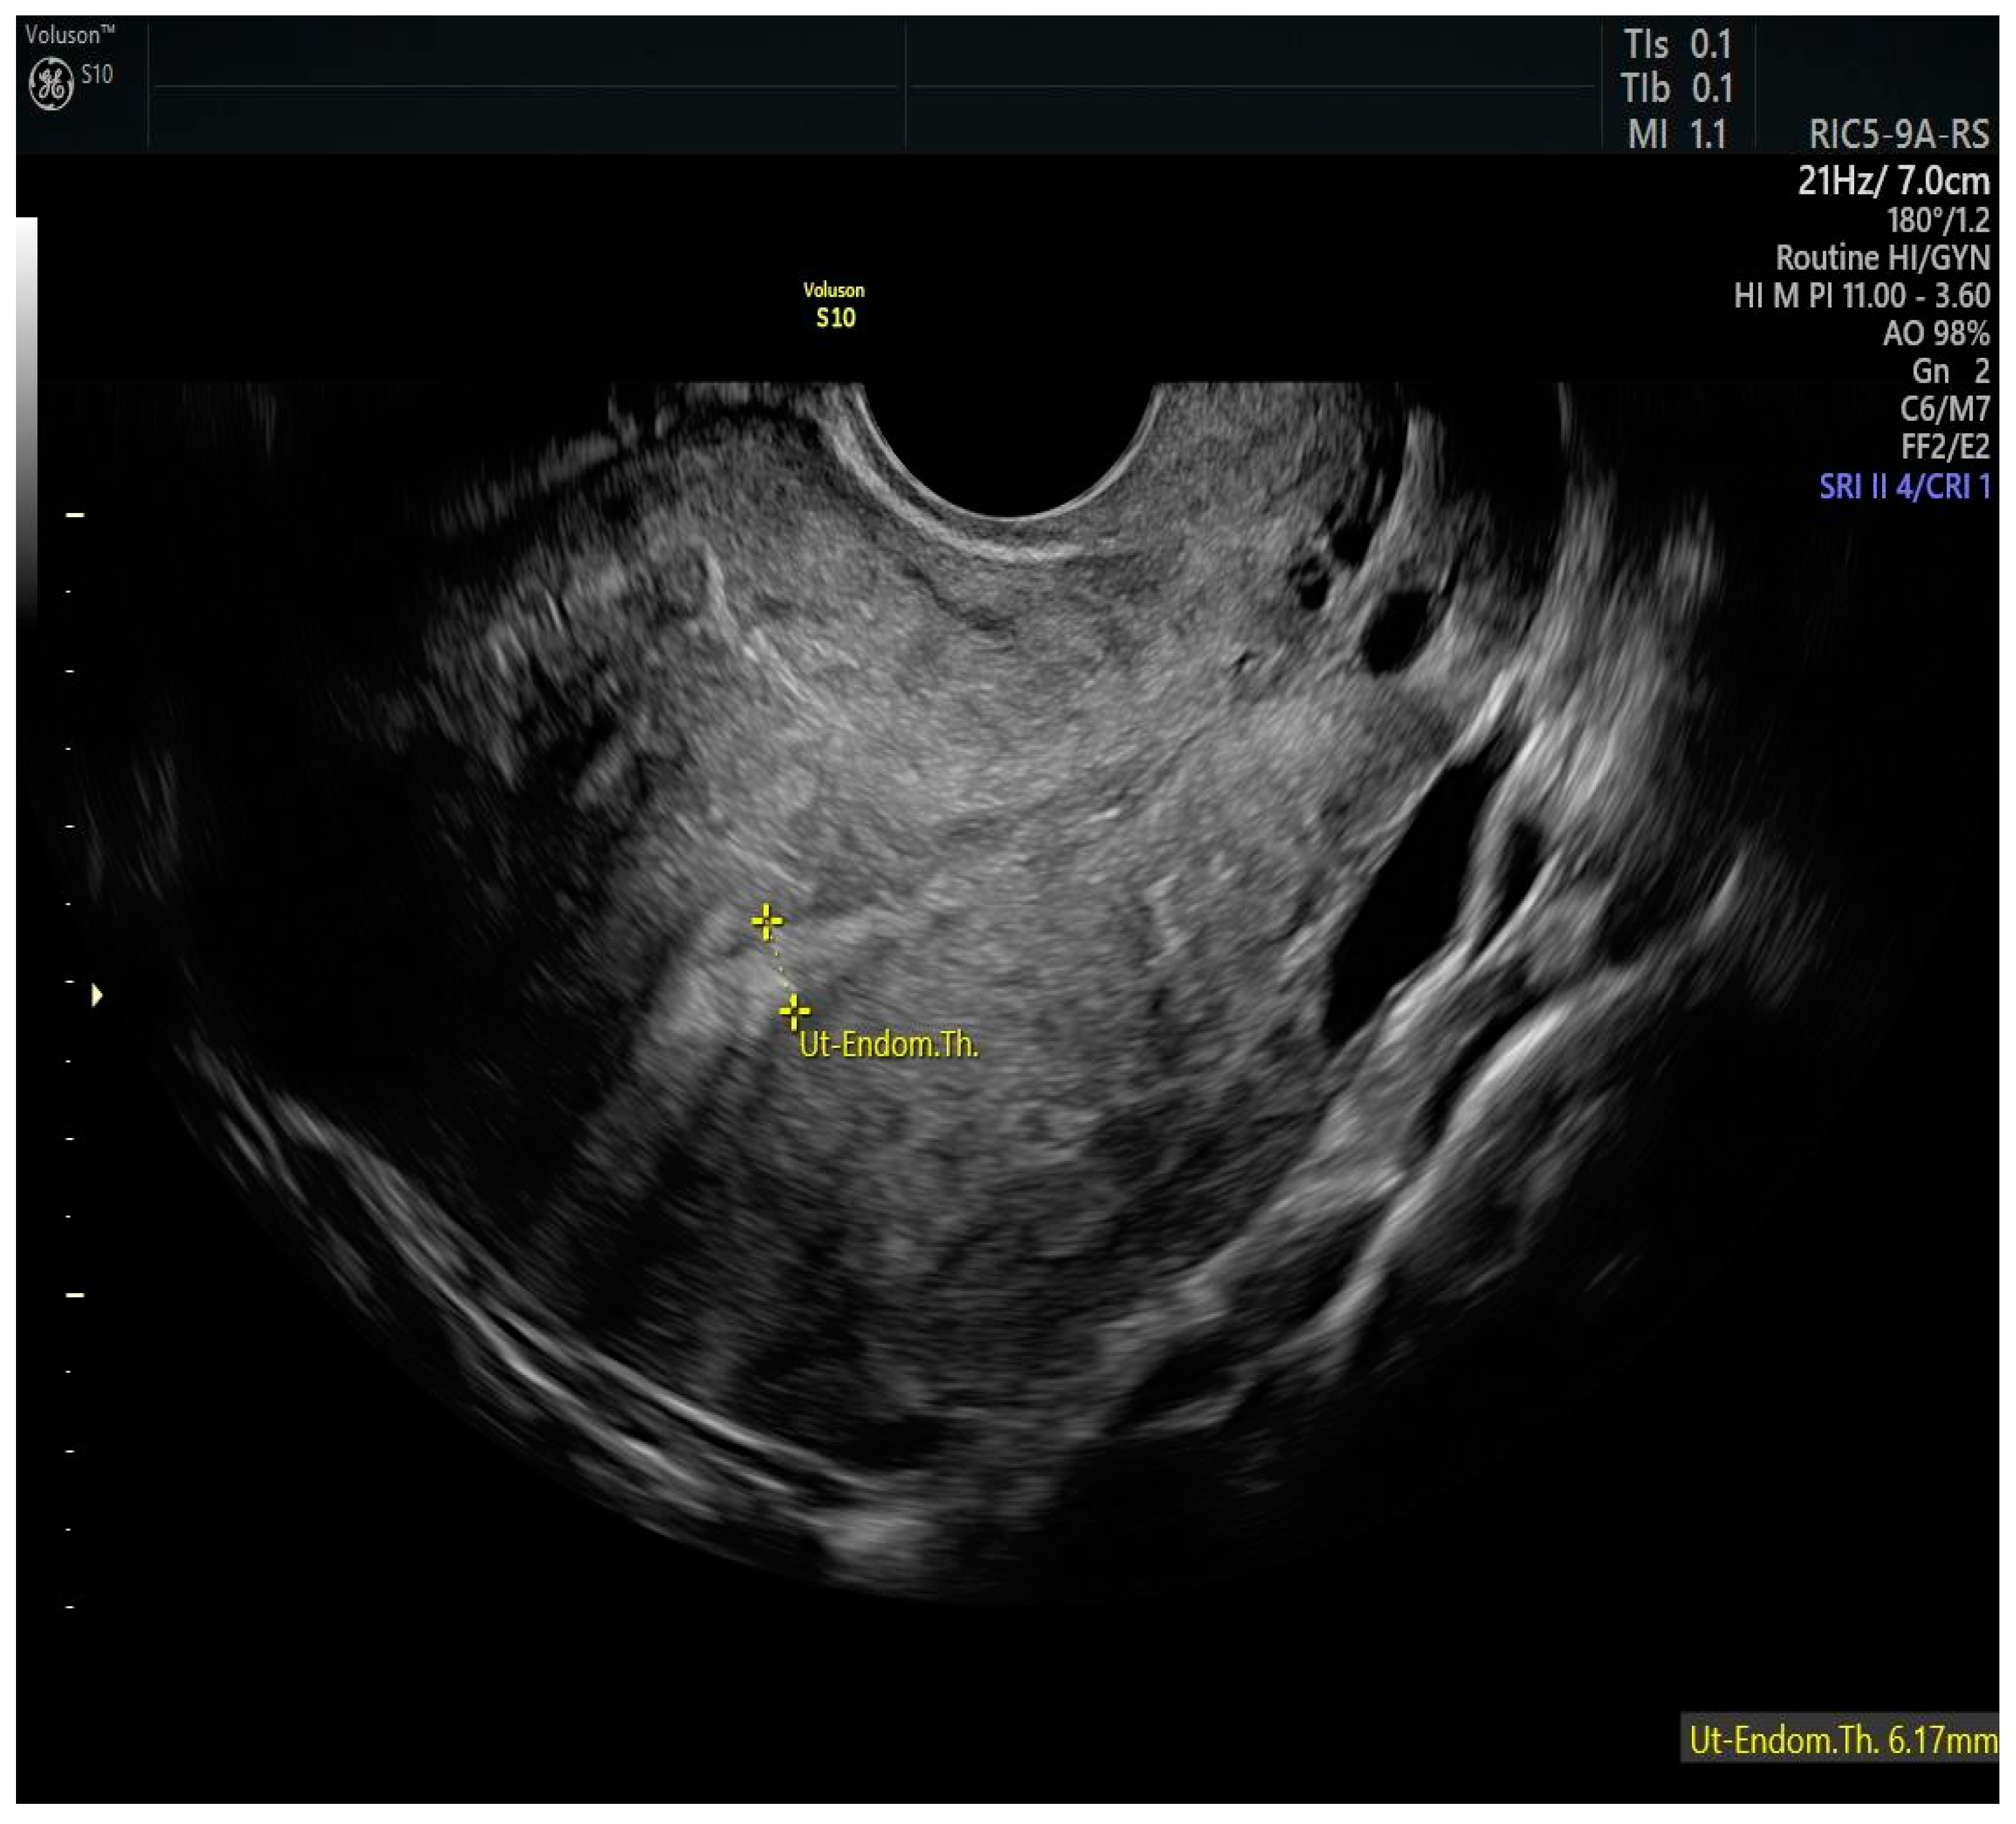

In 2005, Mazzon [39] described the method for the resection of endometrial carcinoma in three steps. In the first surgical step, the neoplastic lesion is resected; in the second step, 4–5 mm of the endometrium adjacent to the lesion is removed; and in the third step, 3–4 mm of the myometrium is removed below the previously removed neoplastic lesion. If confirmed by the pathological examination of G1, the patient can be referred to medical therapy with megestrol acetate 160 mg per day for 6 months. Giampaolino et al. [40] proposed to add additional random endometrial biopsies to the Mazzon technique and replace treatment with megestrol acetate by LNG-IUD placement. Figure 4 shows the case of a woman conservatively treated for endometrial cancer with LNG-IUD, with a thin endometrium.

Figure 4.

Two-dimensional longitudinal scan of the uterus of a patient treated with a levorgestrel-releasing IUD as part of a fertility-sparing regimen. The intrauterine device allows the thickness of the endometrium to remain reduced.